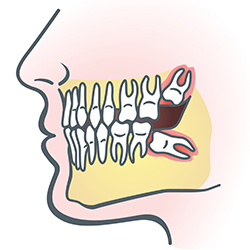

Wisdom Teeth

Wisdom teeth are types of

molars found in the very back of your mouth. These teeth usually appear

in late teens or early twenties but may become impacted (fail to erupt) due to

lack of room in the jaw or angle of entry. When a wisdom tooth is

impacted, it may need to be removed. If it is not removed, you may

develop gum tenderness, swelling or even severe pain. Impacted wisdom

teeth that are partially or fully erupted tend to be quite difficult to clean

and are susceptible to tooth decay, recurring infections and even gum

disease.

Wisdom teeth are typically removed in the late teens or early twenties because there is a greater chance that the teeth's roots have not fully formed and the bone surrounding the teeth is less dense. These two factors can make extraction easier as well as making the recovery time much shorter.

In order to remove a wisdom tooth, your dentist first needs to numb the area around the tooth with a local anesthetic. Since the impacted tooth may still be under the gums and imbedded in your jaw bone, your dentist will need to remove a portion of the covering bone to extract the tooth. In order to minimize the amount of bone that is removed with the tooth your dentist will often "section" your wisdom tooth so that each piece can be removed through a small opening in the bone. Once your wisdom teeth have been extracted, the healing process begins. Healing time varies depending on the degree of difficulty related to the extraction. Your dentist will share with you what to expect and provide instructions for a comfortable, efficient healing process.